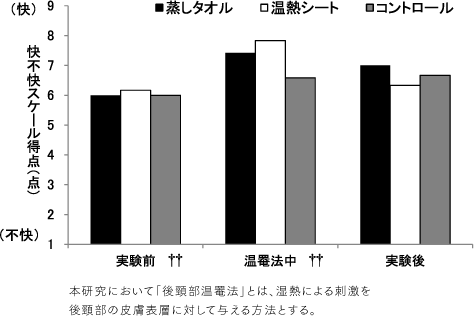

TOPICS

首を温めると良い入眠に繋がる!?

日本看護研究学会の論文によると、「40℃の温熱で15分程度、後傾部(首)温罨法を実施すると、眠気のある快をもたらす。」という研究データが発表されています。

研究結果によると、首を温めることで

心地よさや眠気が手に入る。

という事実!

※【参照論文】後頸部温罨法による自律神経活動と快-不快の変化。

日本看護研究学会雑誌/34 巻 (2011) 2号